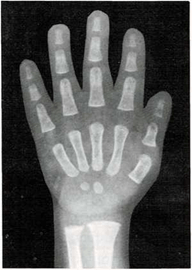

Mi madre me respondió: “Una razón de que lo encuentres blando es que sus huesos no son tan duros como los tuyos. Los niños, al nacer, tienen muy pocos huesos duros. Los huesos de su esqueleto se componen sobre todo de cartílago. Pero las células óseas trabajan sin descanso, y por ello sus huesos crecen y se endurecen muy deprisa. Tus huesos son más largos y duros que los del niño. Los huesos seguirán creciendo y se endurecerán hasta tus veinte años.

Una vez el médico me hizo una radiografía de la muñeca. Quería ver cómo crecían mis huesos. Yo le pregunté cómo era posible que mediante una foto de mis huesos pudiera saber qué le pasaba a mi esqueleto.

El médico me respondió: “Tu muñeca tiene ocho huesos. Pero no todos crecen a la vez. Los huesos de la muñeca de algunos niños crecen más deprisa o más despacio que los de otros niños. Pero los huesos de la muñeca crecen a un mismo ritmo en todos los niños sanos. Si los huesos de tu muñeca salen bien en la radiografía, quiere decir que el resto de los huesos de tu cuerpo también están bien.”

En ella ya se ven claramente los ocho huesos.